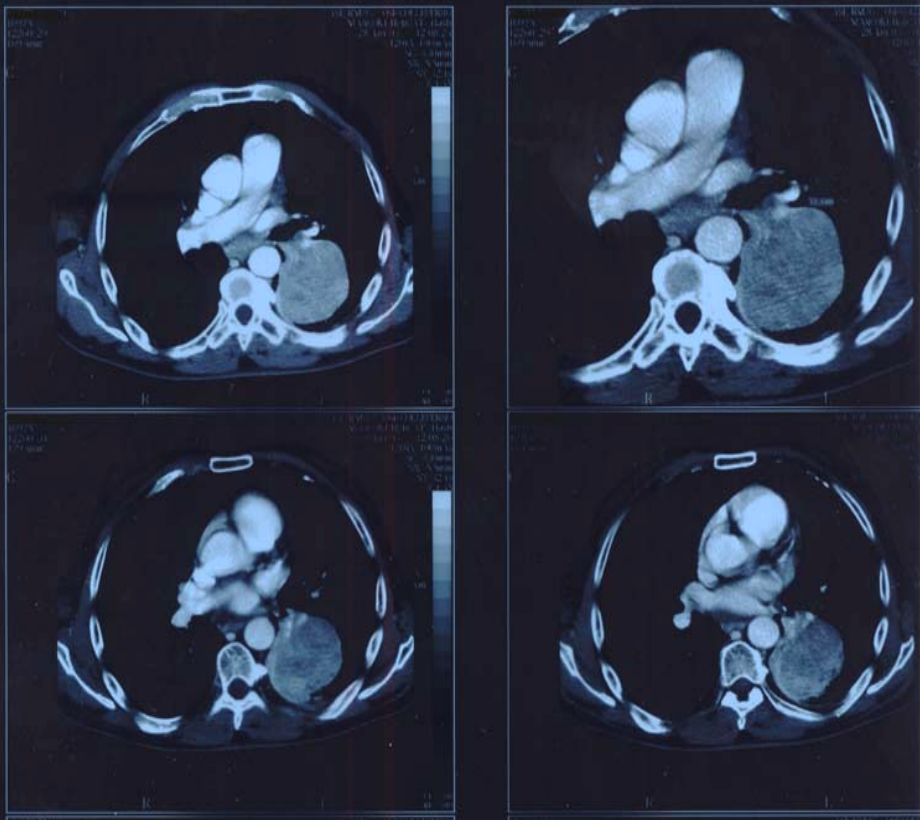

Figure3